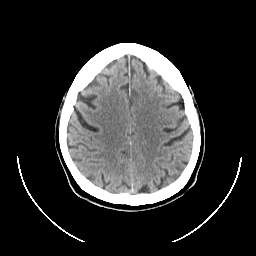

CT Study #1 -- Slice #21